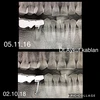

ألم الأسنان

فقدان الأسنان

التهاب الغشاء المخاطي حول الزرعة

تسوس الأسنان

أمراض الأسنان واللثة

نزيف اللثة

التهاب أنسجة ما حول الزرعة